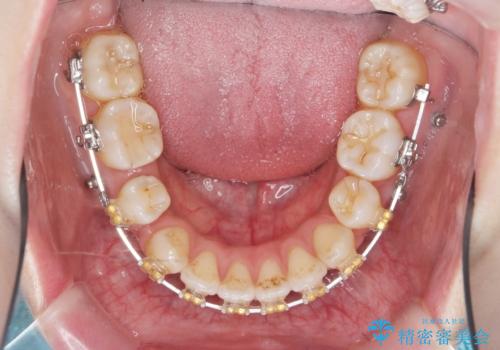

ガタつきと口元の改善 抜歯を伴うワイヤー矯正

- ワイヤー矯正

- 唇の閉じづらさと、前歯のがたつきの改善を希望され来院されました。

抜歯を行わなくてもなんとか並べられる歯並びですが、唇の閉じづらさをしっかりと改善するため抜歯を伴うマルチブラケット矯正を行うこととしました。

前歯をしっかりと後方に引いたことで、唇は閉じやすくなり、仕上がりに満足いただくことができました。